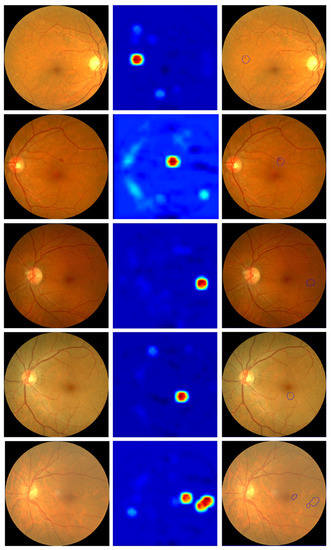

The method explored in Section 2.4 was applied to a series of images to verify its performance. Some examples are shown in Figure 5.

This figure also shows an automatic detection of the areas of interest based on the activation maps (third column). It should be noted that, despite obtaining visually positive results, there is a major drawback when analyzing them with an automatic method that makes it very difficult to obtain an automatic detection/segmentation of all the signs of diabetic retinopathy. Specifically, a map of the “importance” measure of each pixel for classification is obtained, but this value of “importance” is not bounded to any specific range. Therefore, the decision as to what value a pixel has to have for it to be a sign of DR is given by the whole range of values obtained for each individual image. This lack of reference is the main difficulty, as it makes it necessary to use an additional algorithm to segment or cluster the resulting activation image to automatically detect areas of interest. The algorithm used in Figure 5 is a contour detection algorithm for areas that have pixels with an “importance” value of at least 75% of the image range. It can be seen that, although it is able to detect areas of interest in all images, it fails to obtain all signs of retinopathy despite the fact that some of them are qualitatively visible in the activation image.

Figure 5. First column: input retinography. Second column: multiscale activation maps. Third column: automatic selection of areas of interest based on activation maps.